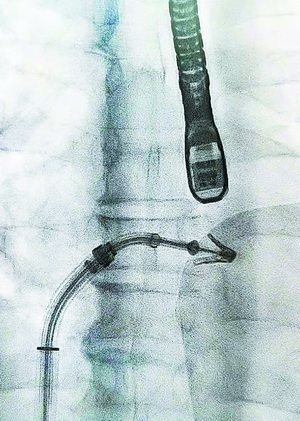

钳夹导管近心端,夹闭血流.